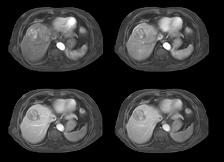

With 4D FreeBreathing, you can now offer free-breathing MRI liver to a broader population, while improving imaging confidence and the patient experience. This allows you to address patients who have difficulty holding their breath or find it difficult to follow breathing instructions.

4D FreeBreathing – Dynamic 3D T1w TFE Resolution: 1.6 X 1.6 X 5.0 mm Scan time: 3:16min Magnet ic Resonance